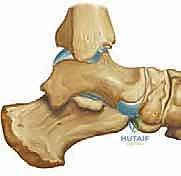

لفهم أهمية جراحة كوتون، يجب علينا أولاً الغوص في التركيب التشريحي المعقد للقدم البشرية. تتكون القدم من شبكة مذهلة من العظام، الأربطة، والأوتار التي تعمل بتناغم تام لتوفير الدعم، التوازن، والحركة. العمود الإنسي للقدم (Medial Column) يتكون من عظم الكاحل، العظم الزورقي، العظام الإسفينية، ومشط القدم الأول. هذا العمود هو المسؤول الأساسي عن تشكيل القوس الطولي الداخلي للقدم.

جراحة كوتون هي عبارة عن إجراء جراحي دقيق يتضمن عمل شق أو قطع في العظم الإسفيني الإنسي (Medial Cuneiform)، ثم فتح هذا الشق لتكوين فجوة على شكل "وتد" (Wedge). يتم بعد ذلك ملء هذه الفجوة بطعم عظمي (Bone Graft) وتثبيتها. النتيجة المباشرة لهذا الإجراء هي دفع مشط القدم الأول إلى الأسفل (Plantarflexion)، مما يعيد القوس الداخلي للقدم ويصحح تشوه مقدمة القدم الأروح.

سُميت هذه الجراحة نسبة إلى الجراح الرائد F.J. Cotton، الذي وصف في عام 1936 أهمية استعادة التلامس بين رأس مشط القدم الأول والأرض لضمان ثبات القدم. وقد أدرك كوتون أن هذا "الوتد" العظمي يعيد بناء "مثلث الدعم" الأساسي للقدم.